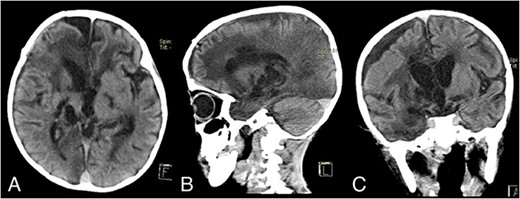

On admission, his GCS was E2M4V2 with a blood pressure of 88/58 mmHg, heart rate of 94 times per minute, respiratory rate of 33 times per minute, temperature of 36.6°C, and oxygen saturation of 86%. Auscultation revealed a systolic murmur. The patient also had cyanosis and clubbing fingers. The patient was malnourished, with a weight of 13 kg and a height of 98 cm. His chest X-ray revealed a cardiomegaly. Head CT scan revealed a hypodense lesion on the right frontotemporoparietal lobe with a size of 5.7 × 6.5 × 7.7 cm with tentacle-like edema on its surrounding, which gave a ring-enhancement after contrast administration (Fig. 1A–C). On echocardiography, there was a significant VSD with a bidirectional shunting.

Admission contrast head CT scan showing a large hypodense lesion with ring-enhancement on the right frontotemporoparietal lobe; (A) axial view; (B) sagittal view; (C) coronal view.